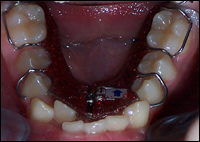

Fig 3 & 4: Upper and lower Schwartz Appliances were fabricated.